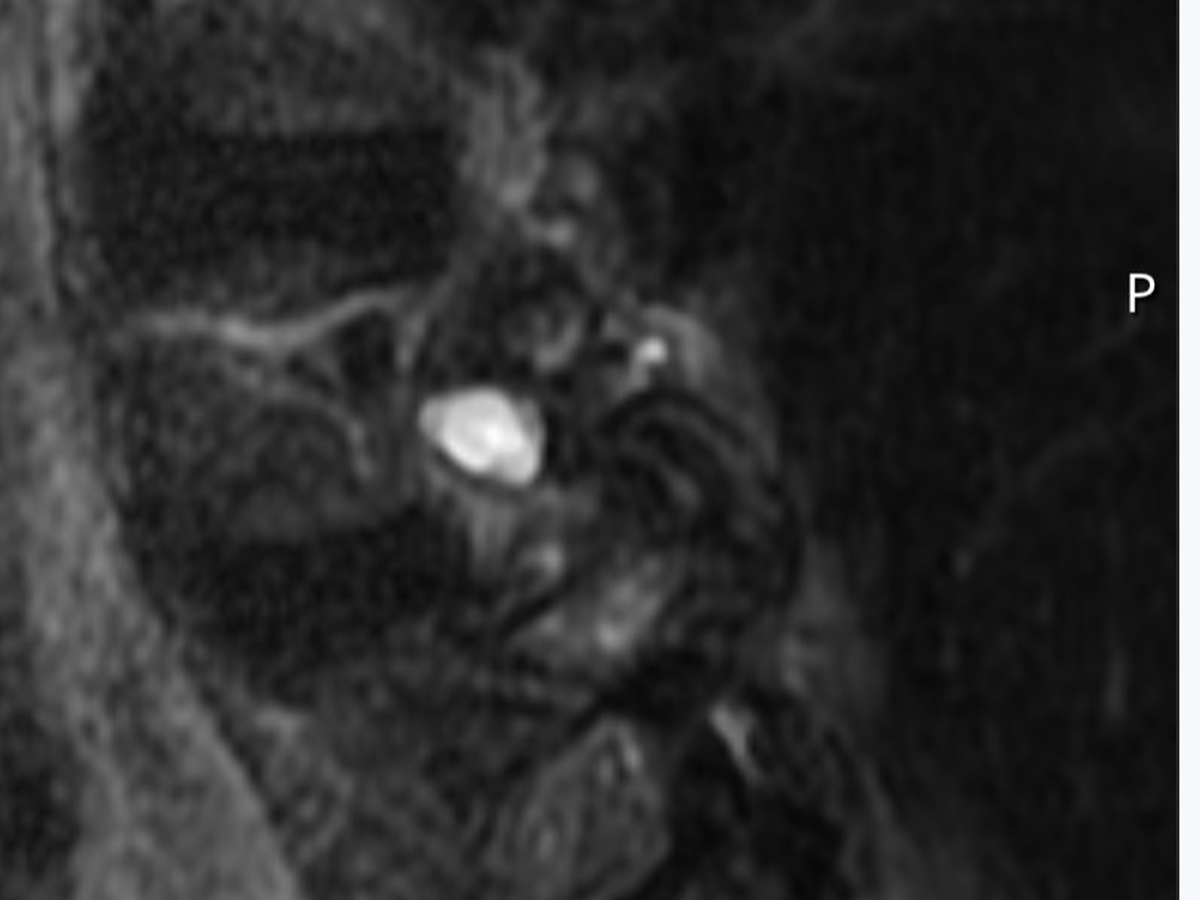

Here is the MRI of the growth from two views. As you can see it's right on the spine itself pushing on the nerves simulating a ruptured disk.

Surgery itself is relatively simple. He will cut through the back muscles and remove the growth as long as it has not grafted to the nerve root. He will remove bone to open the chamber where the root feeds the nerves to my right leg and hip.